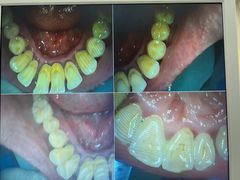

• 牙博士口腔品牌连锁(杨浦店)

• -牙博士口腔品牌连锁(杨浦店)

橘子_ | 22-06-26